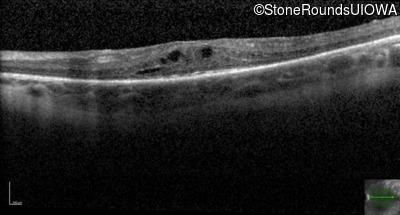

Optical Coherence Tomography - Right - 20/60 -1

Exemplar / OCT Stack